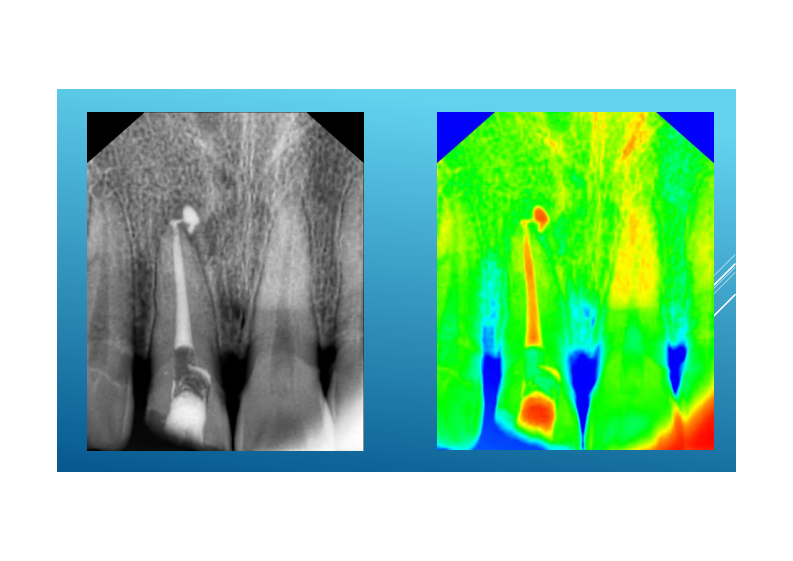

现代根管治疗的临床步骤最最最终版.pdf